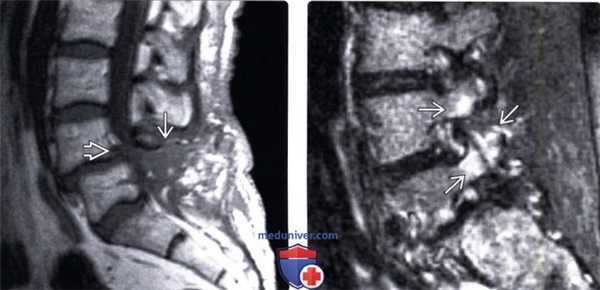

(Слева) Т1-ВИ, сагиттальная проекция: легкий спондилолистез L4 после перенесенной ляминэктомии нижнепоясничного отдела позвоночника.

(Справа) На сагиттальном STIR МР-И отмечается гиперинтенсивный отек костного мозга смежных суставных отростков и корней дуг L4-L5 позвонков. I тип изменений сигнала костного мозга может наблюдаться при дегенеративной артропатии дугоотростчатых суставов и служить отражением их биомеханической перегрузки в условиях уменьшения высоты межпозвонкового диска и сформировавшегося на этом фоне спондилолистеза.

(Слева) Т2-ВИ, сагиттальная проекция: признаки многоуровневого спондилеза шейного отдела позвоночника с антеролистезом СЗ позвонка, стенозом спинномозгового канала на этом уровне и компрессией спинного мозга. На уровне стеноза видны признаки миеломаляции спинного мозга, развившейся на фоне постоянной травматизации его в условиях стенозироваиного канала и проявляющейся усилением Т2-сигнала.

(Справа) КТ, сагиттальный-срезе (костный режим): задний край тела L5 находится практически на одном уровне с передним краем S1. Хорошо виден дефект межсуставной части дуги, а также признаки выраженного стеноза межпозвонкового отверстия.

(Слева) КТ, фронтальный срез: многоуровневое дегенеративное поражение межпозвонковых дисков с формированием латерального листеза. Обратите внимание на признаки склерозирования костей по ходу линий нагрузки вдоль правой и левой половин позвоночника.

(Справа) Т1-BИ, сагиттальная проекция: у пациента, сбитого грузовиком, видны признаки спондилолистеза на уровне L5/S1 сегмента. Позади тела L5 и между задними элементами L5 и S1 определяется гематома, характеризующаяся неоднородным низким и высоким сигналом.